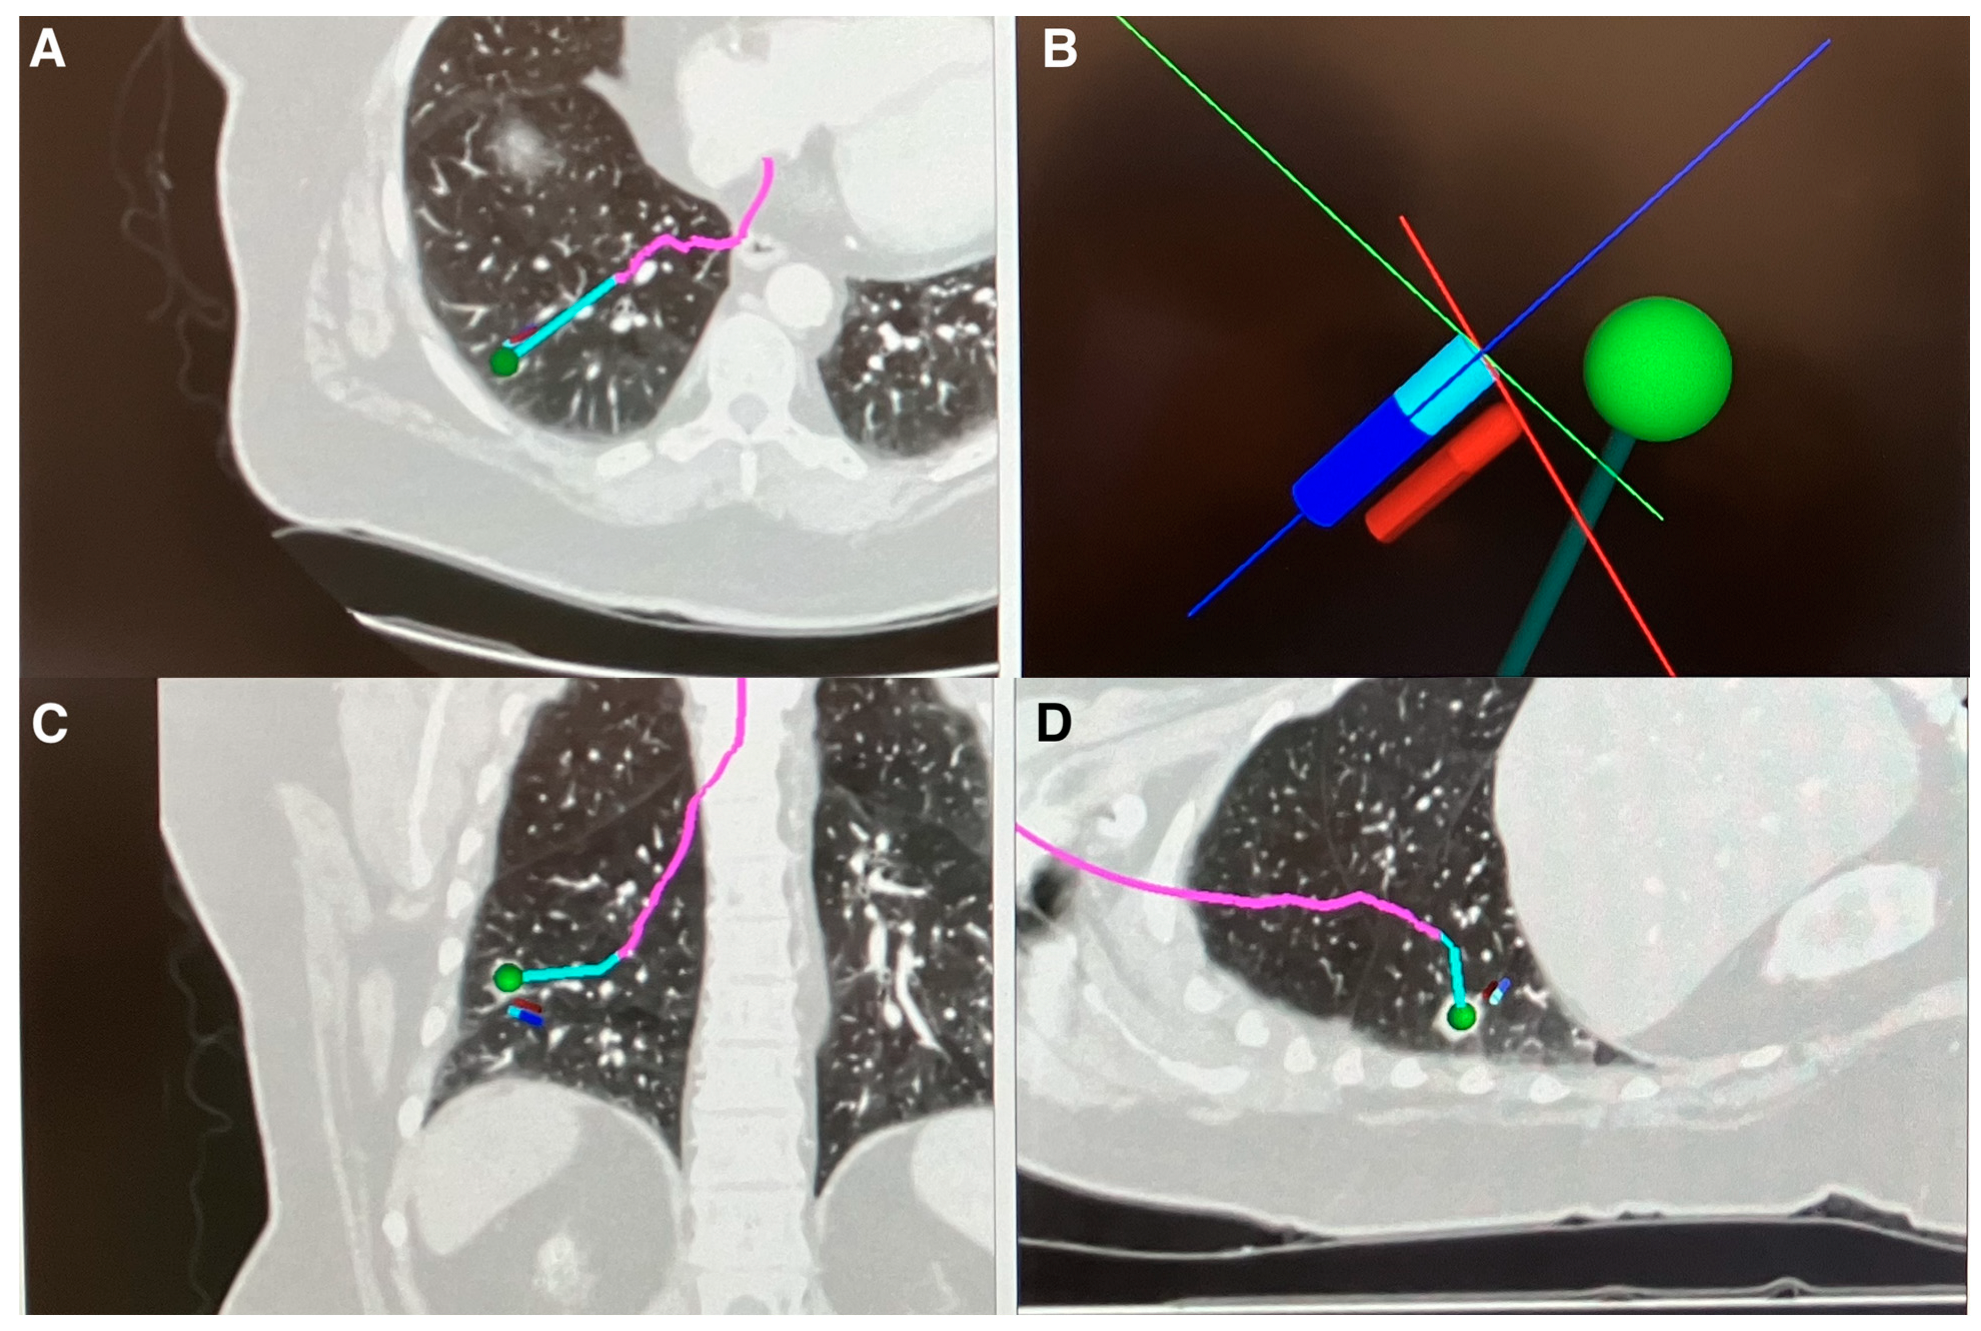

- Reisenauer, J.; Duke, J.D.; Kern, R.; Fernandez-Bussy, S.; Edell, E. Combining Shape-Sensing Robotic Bronchoscopy with Mobile Three-Dimensional Imaging to Verify Tool-in-Lesion and Overcome Divergence: A Pilot Study. Mayo Clin. Proc. Innov. Qual. Outcomes 2022, 6, 177–185. [Google Scholar] [CrossRef]

- Kalchiem-Dekel, O.; Fuentes, P.; Bott, M.J.; Beattie, J.A.; Lee, R.P.; Chawla, M.; Husta, B.C. Multiplanar 3D fluoroscopy redefines tool-lesion relationship during robotic-assisted bronchoscopy. Respirology 2021, 26, 120–123. [Google Scholar] [CrossRef]

- Sadoughi, A.; Virdi, S. Mobile 3D Intraprocedural Fluoroscopy in Combination with Ultrathin Bronchoscopy for Biopsy of Peripheral Lung Nodules. J. Bronc-Interv. Pulmonol. 2021, 28, 76–80. [Google Scholar] [CrossRef] [PubMed]